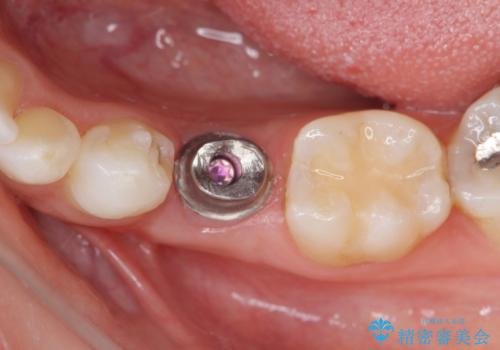

- 44万円(インプラント・チタンカスタムアバットメント・ジルコニアクラウン・仮歯)費用は治療当時の料金となります

乳歯の抜去後、インプラントを用いてしっかりと咬合機能を回復することができました。